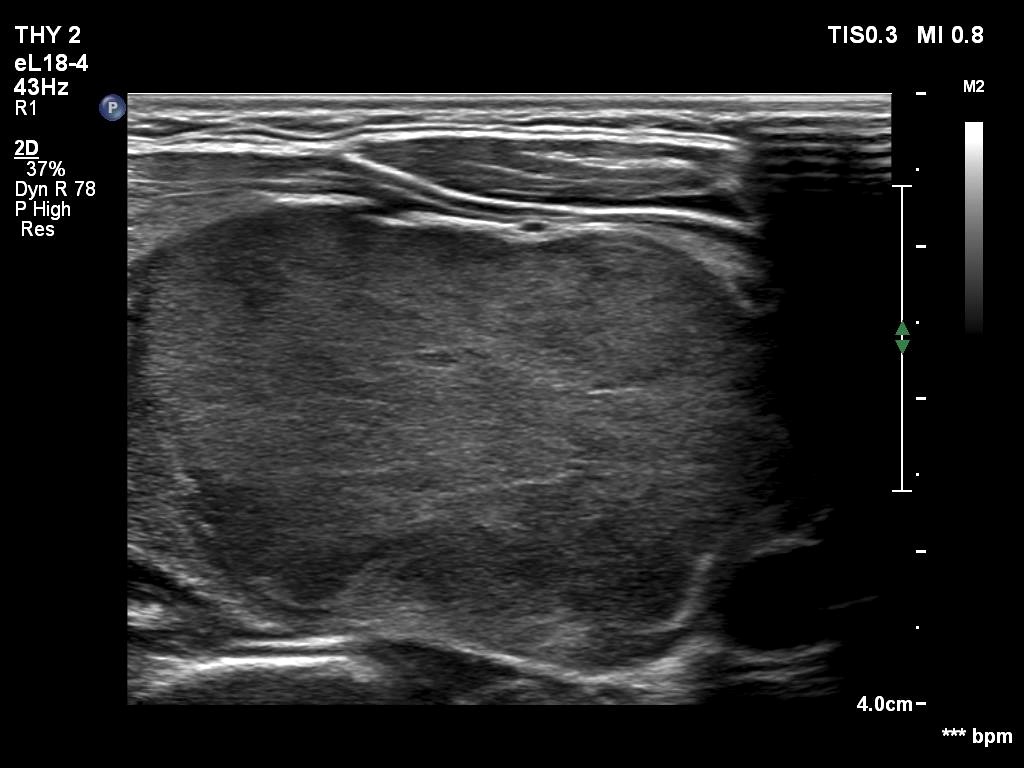

Third examination - seven years after the first examination (third row of images)

Clinical presentation: The patient hasn't been operated on, yet. She came to a repeat examination because of neck complaints, she felt pressure when lying down.

Palpation: a firm nodule in the left lobe.

Laboratory tests: TSH 1.70 mIU/L.

The dimensions of the nodule in the left lobe were 41x25x50 mm, width, depth, length, respectively, the volume of the lesion was 26.8 mL.

FNA resulted in follicular tumor.

Histopathology disclosed minimally invasive follicular cancer. The largest diameter was measured 55 mm. Both capsular and vascular invasions were found microscopically.